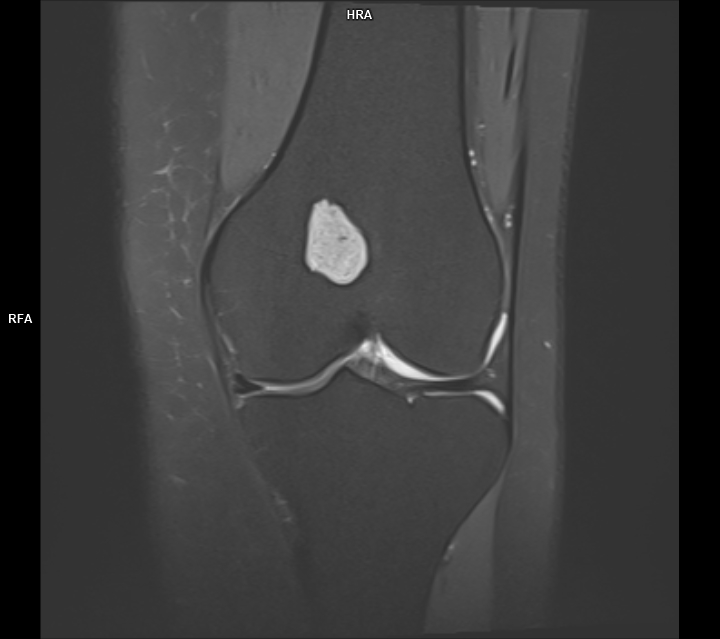

CAZ nr 44 Encondrom femural distal

Figura 1: achiziție în plan coronal în ponderație PD cu saturația grăsimii

Discuție caz nr 44: Encondromul este o tumora benignă cu origine cartilaginoasă; cazul prezentat evidențiază o leziune net delimitată în hipersemnal PD, hiposemnal T1, fără restricție de difuzie, ce nu modifica semnalul țesutului osos de vecinătate si se dezvoltă de o parte şi de alta a cartilajului de creștere.